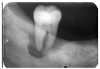

In Figure 4, recurrent caries appears at the mesial of tooth #3 and #4, and the distal of tooth #28. Also, note areas of interproximal caries on teeth #5-6.

Figure 4 - Recurrent Caries

Figure 4